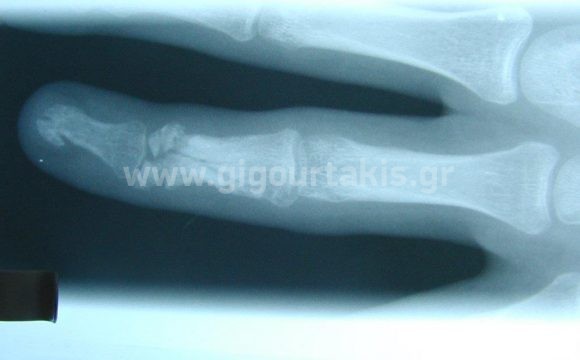

ΚΑΤΑΓΜΑ ΦΑΛΑΓΓΩΝ ΔΑΚΤΥΛΩΝ ΧΕΙΡΟΥΡΓΙΚΑ ΕΞΩΤΕΡΙΚΗ ΟΣΤΕΟΣΥΝΘΕΣΗ ΠΕΡΙΣΤΑΤΙΚΟ 1 01. ΑΚΤΙΝΟΓΡΑΦΙΑ 02. ΑΚΤΙΝΟΓΡΑΦΙΑ 03. 04.ΑΡΧΙΚΗ ΚΑΜΨΗ ΔΑΚΤΥΛΩΝ 05.ΑΡΧΙΚΗ ΚΑΜΨΗ ΔΑΚΤΥΛΩΝ 06.ΤΕΛΙΚΗ ΚΑΜΨΗ ΔΑΚΤΥΛΩΝ 07.ΤΕΛΙΚΗ ΕΚΤΑΣΗ ΔΑΚΤΥΛΩΝ Στις κατηγορίες:ΑΝΩ ΑΚΡΟ, ΕΞΩΤΕΡΙΚΗ ΟΣΤΕΟΣΥΝΘΕΣΗ, ΑΚΡΑ ΧΕΙΡΑ, ΚΑΤΑΓΜΑ ΦΑΛΑΓΓΩΝ ΔΑΚΤΥΛΩΝ, ΧΕΙΡΟΥΡΓΙΚΑ